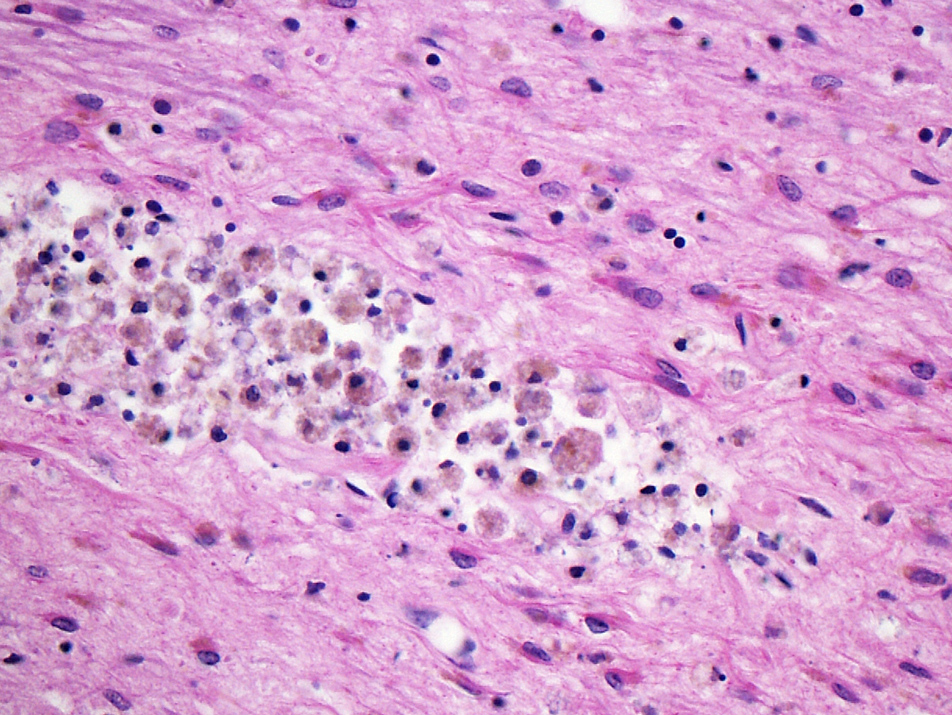

- Chronic (15 days - years)

- Cavitated lesion with vessels and macrophages surrounded by a glial scar

- Reactive astrocytes in the edge of the cavitation

- Can be piloid gliosis with Rosenthal fibers, particularly in brainstem infarcts

- Scattered hemosiderin laden macrophages typically present

- Vascular dementia

- Diagnosis is based on the absence of a primary neurodegenerative disease known to cause dementia (e.g., Alzheimer disease, Lewy body dementia)

- Multivariable model based likelihood showed that the presence of 1 or 2 microinfarcts on routine neuropathological sections indicates a burden of hundreds of microinfarcts in that brain (Neurology 2013;80:1365)

- Binswanger disease

- Multiple infarcts, typically chronic, with associated white matter rarefaction, myelin loss, loss of oligodendroglia and reactive gliosis

- Subcortical U fibers are usually spared

- Penetrating arteries' walls are markedly thickened and hyalinized with enlarged perivascular spaces

- CAA and CADASIL are uncommonly associated as the underlying cause of Binswanger disease (Neurology 1995;45:626, J Neurol Sci 2010;299:9)

Microscopic (histologic) images